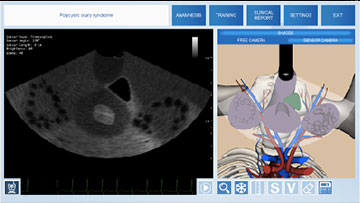

Симулятор ультразвуковой диагностики MedVision SonoVision

Виртуальный симулятор ультразвуковых исследований (УЗИ) SonoVision – обучающий тренажер на единой платформе обеспечивающий освоение основных навыков проведения ультразвукового исследования, понимание и идентификацию различных заболеваний и патологии внутренних органов человека.

SonoVision – симулятор ультразвуковой диагностики является инструментом для профессионального изучения медицины. Это виртуальный симулятор для отработки навыков ультразвуковой диагностики. Он используется как студентами, так и практикующими специалистами в клиниках и больницах. Симулятор ультразвуковой диагностики – прекрасное дополнение к традиционному обучению и повышению квалификации медицинского персонала.

Новое поколения симулятора УЗИ гарантирует высочайший уровень детализации внутренних органов, а работа с анатомически корректным манекеном обеспечивает реалистичные тактильные ощущения и визуальную картину при выполнении вмешательств. В симуляторе реализовано более 40 клинических сценариев.

Модуль базовых навыков в гинекологии

Модуль по абдоминальному УЗИ мочевого пузыря (для женщин) и органов женского таза

- Обучающий модуль по ультразвуковому исследованию мочевого пузыря (для женщин) + органов женского таза (матка + яичники) с помощью абдоминального датчика

- Обучающий модуль базовых навыков в гинекологии